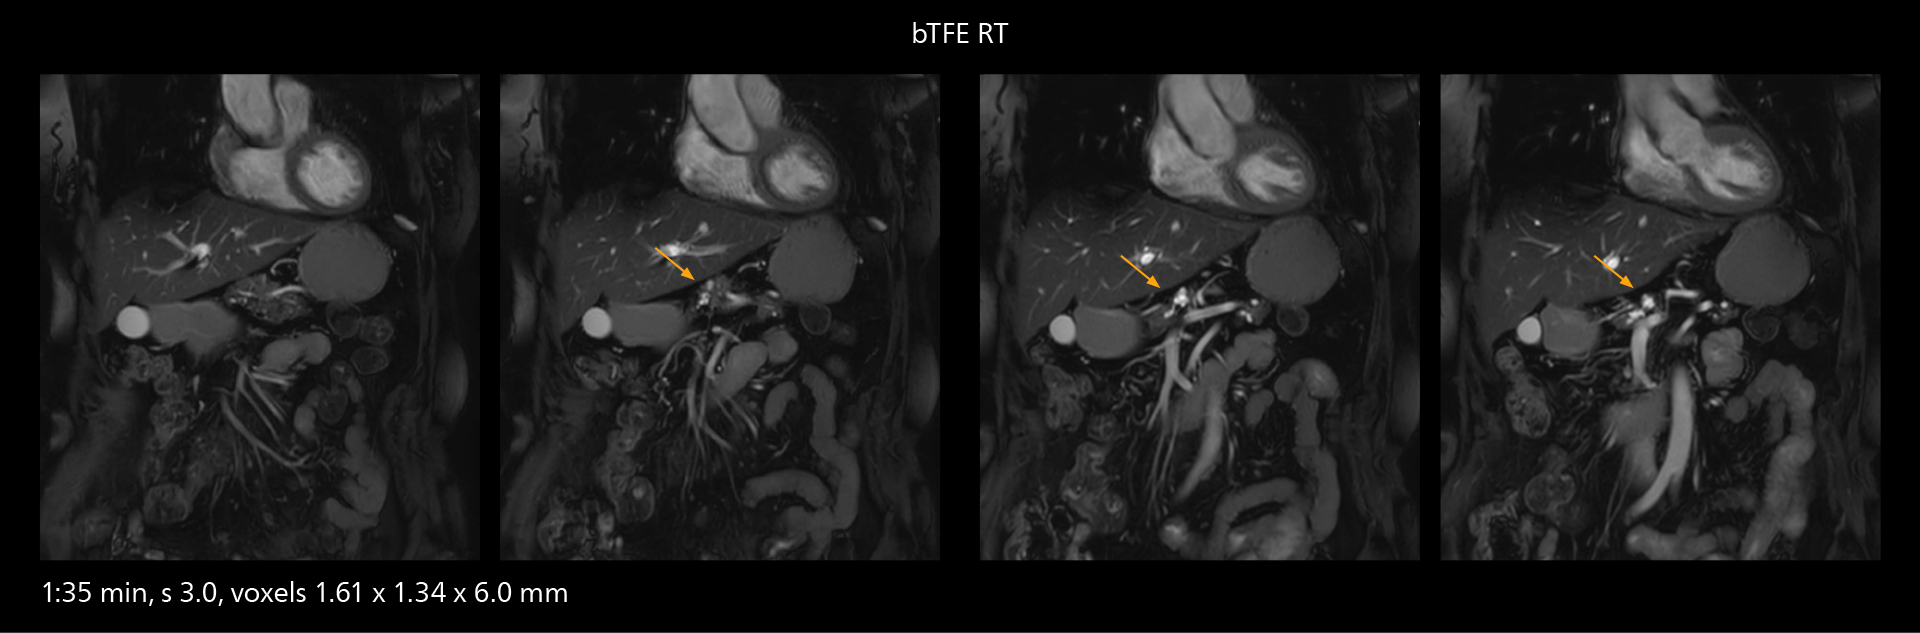

Fast whole body DWIBS examination

With SmartPath to Elition X the team can obtain excellent quality DWIBS imaging and reduce imaging time. Other sequences also fit in the examination slot. This case shows left paravertebral neurogenic tumor and Th10 vertebral hemangiomas.

The value of the Elition X gradients is also evident in DWIBS studies. “The fact that we can consistently obtain distortion‐free DWIBS while reducing imaging time at three coronal stations is excellent,” Dr. Makuuchi says. “In these patients, it’s also important that the application of Compressed SENSE to T2‐weighted, STIR and mDIXON sequences has no impact on the examination time of whole‐body imaging. As a result of the increased speed and higher image quality we realize, DWIBS studies have now become routine examinations.”